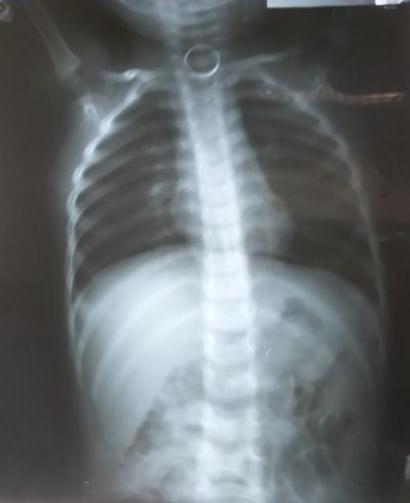

11/12/2017 18:24Chiếc móc khóa nằm trong thực quản bé trai hai tuổi

Bé được người nhà đưa vào viện cấp cứu do nuốt một vòng móc khóa bằng kim loại. Bệnh nhi vẫn tỉnh táo, chưa có dấu hiệu nguy hiểm. Kết quả chụp X-quang phát hiện có một dị vật hình tròn nằm trong thực quản ngang đốt sống cổ số 6-7 của bé.

Các bác sĩ đã hội chẩn quyết định nội soi gắp dị vật cho cháu. Sau 10 phút tiến hành thủ thuật, kíp mổ đã lấy ra một móc khóa kim loại có đường kính khoảng 2 cm. Hiện sức khỏe cháu bé đã ổn định.

Các bác sĩ cảnh báo, dị vật đường thở thường gặp nhiều ở trẻ em, nhất là trẻ nhỏ tuổi. Hóc dị vật có thể gây nguy hiểm đến tính mạng nạn nhân nếu không được xử trí kịp thời. Phụ huynh không nên cho trẻ cầm các loại đồ chơi hay vật nhỏ bé dễ bỏ vào miệng ngậm. Tập cho trẻ thói quen không được ngậm bất cứ thứ gì trong miệng. Nếu bị hóc hoặc nghi hóc dị vật vào đường thở, đưa trẻ đến ngay cơ sở y tế để được xử trí kịp thời.